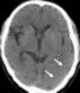

Subjacent acute cerebral infarction

Focal leptomeningeal enhancement